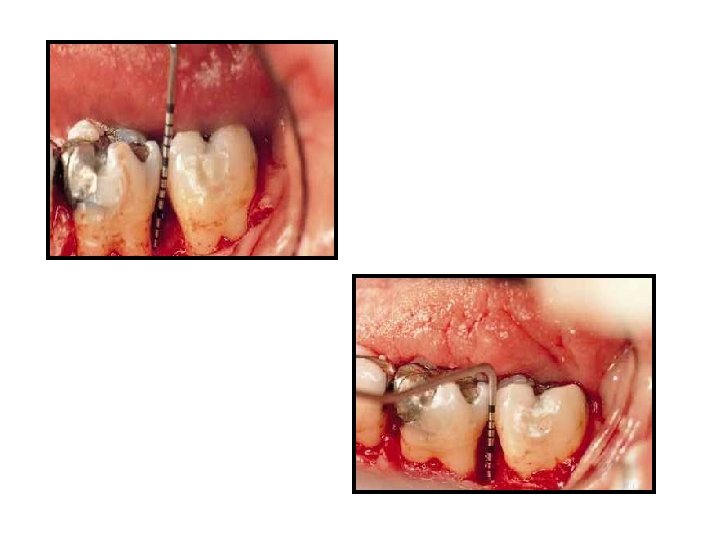

Flap design A sulcular incision full thickness flap is reflected. A three wall intrabony defect is visualized at the distal of the first molar.

Defect or root debridement Rotary instrumentation using a multifluted surgical length bur on a high-speed handpiece is needed to gain access to the depth of the lesion and to plane the root surface, which is subsequently treated with citric acid (p. H 1).

Placement of demineralized freeze-dried bone allograft is accomplished with light incremental pressure so that the graft overfills the defect. The root surface has been treated with citric acid (p. H 1) and the defect has been decorticated.